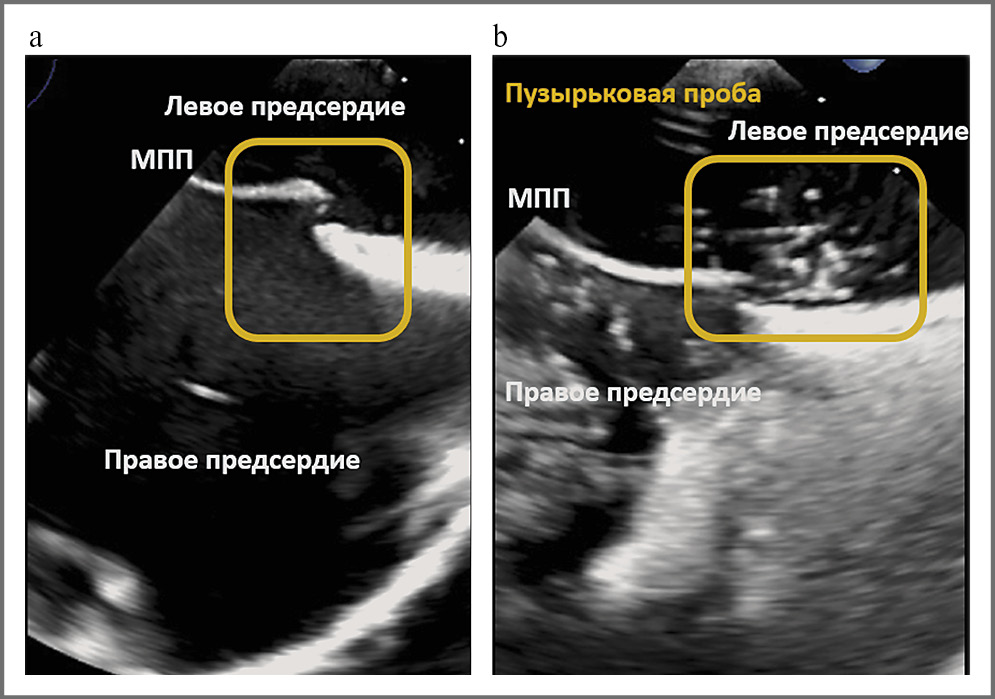

Для оценки эмбологенности ООО используют чреспищеводную ЭхоКГ и транскраниальную допплерографию (ТКД). Чреспищеводная ЭхоКГ обеспечивает визуализацию формы овальной ямки, анатомии ООО, межпредсердной перегородки и близлежащих структур. К сожалению, далеко не всегда в режиме цветового допплеровского картирования удается визуализировать ООО даже с использованием низких скоростей кровотока – чувствительность 89%, специфичность 92% [24]. В связи с этим всем пациентам с подозрением на парадоксальный сброс крови через овальное окно необходимо проведение чреспищеводной ЭхоКГ с внутривенным контрастированием. Сложность правильного выполнения пробы Вальсальвы не всегда позволяет оптимально выявить шунтирующий поток справа налево [19, 20]. Надежным методом идентификации шунтирующего потока и оценки его значимости является транскраниальная допплерография [5, 19–21]. Чувствительность и специфичность этого метода составляют 96 и 93% соответственно [25]. Признаками межпредсердного сброса тяжелой степени являются проникновение ≥20 пузырьков воздуха из правого в левое предсердие по данным чреспищеводной ЭхоКГ, >10 высокоинтенсивных сигналов или «занавес» при ТКД [20]. У пациентки А. по данным ТКД (рис. 3) и чреспищеводной ЭхоКГ (рис. 4) с «пузырьковой» пробой выявлен межпредсердный сброс справа налево через ООО тяжелой степени.

Рис. 4. Чреспищеводная ЭхоКГ (а) с «пузырьковой» пробой (b) во время маневра Вальсальвы. Прохождение более 30 пузырьков воздуха через овальное окно.

Учитывая наличие межпредсердного сброса справа налево тяжелой степени и высокий суммарный балл по шкале RoPE, можно рассматривать ООО как наиболее вероятную причину повторных ИИ в представленном клиническом случае. До недавнего времени практически единственным механизмом развития инсульта на фоне ООО считали парадоксальную эмболию из вен нижних конечностей, которые, как мы уже отметили, оказались интактны у обсуждаемой больной. В последнее время большое внимание стали уделять анатомическим особенностям предсердий, повышающим риск тромбообразования. К ним относят аневризмы межпредсердной перегородки и ее гиперподвижность, ширину и длину тоннеля ООО, евстахиев клапан, наличие сети Киари [20]. Длина тоннеля ООО у нашей больной А. составила 0,8 см, что классифицирует тоннель как длинный, ширина при пробе Вальсальвы оказалась равна 0,6 см, что соответствует значимому расширению. Таким образом, механизмом ИИ в нашем клиническом примере следует считать стаз крови с образованием тромба in situ в тоннеле ООО с развитием кардиоэмболии при повышении давления в правых отделах сердца во время интенсивного кашля, фактически имитирующего маневр Вальсальвы. Соответственно, на момент завершения поиска, установившего причину инсульта, диагноз ESUS утратил актуальность и следовало говорить о кардиоэмболическом подтипе ИИ, связанном с ООО. В пользу этой гипотезы свидетельствует недавно опубликованная работа C. Yan и соавт. [26], где 11 пациентам, 10 из которых перенесли криптогенный инсульт, а у одного отмечалась мигренозная головная боль, выполнена оптическая когерентная томография высокого разрешения в области овального окна. У всех 11 пациентов (100%) внутри овального окна обнаружены множественные тромбы (среднее число 12,6 на пациента, средний общий объем тромба – 0,04 мм3). Кроме того, у 9 человек зафиксирована неровность поверхности эндокарда (у 3 пациентов на неровных поверхностях эндокарда обнаружены тромбы in situ), а еще у 3 пациентов имели место надрывы эндокардиальной поверхности. Ни у одного бессимтомного пациента в контрольной группе (n=7) подобные явления не наблюдали. Таким образом, выявленные микротромбы в области овального окна могут быть образованы in situ либо быть остатками парадоксальных тромбов венозного происхождения.